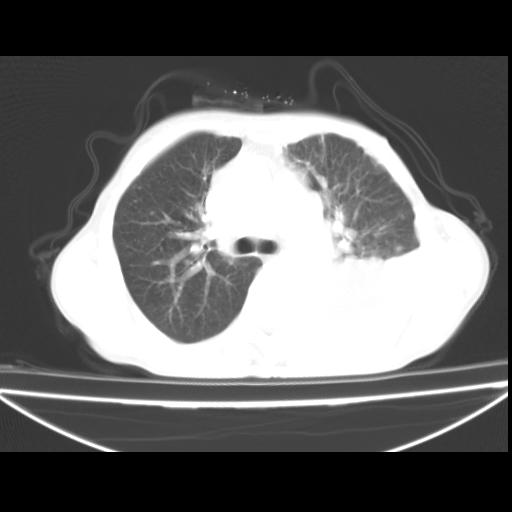

以下是引用随光逐影在2010-3-24 19:15:00的发言:[br]结合病史,考虑双肺及纵隔淋巴结多发转移、左侧胸膜转移并左侧大量胸水,左下肺膨胀不全。

以下是引用zxl51642在2010-3-24 18:49:00的发言:[br]结合乳腺癌术后病史,考虑双肺及纵隔淋巴结多发转移、左侧胸膜转移并左侧大量胸水、左下肺膨胀不全。